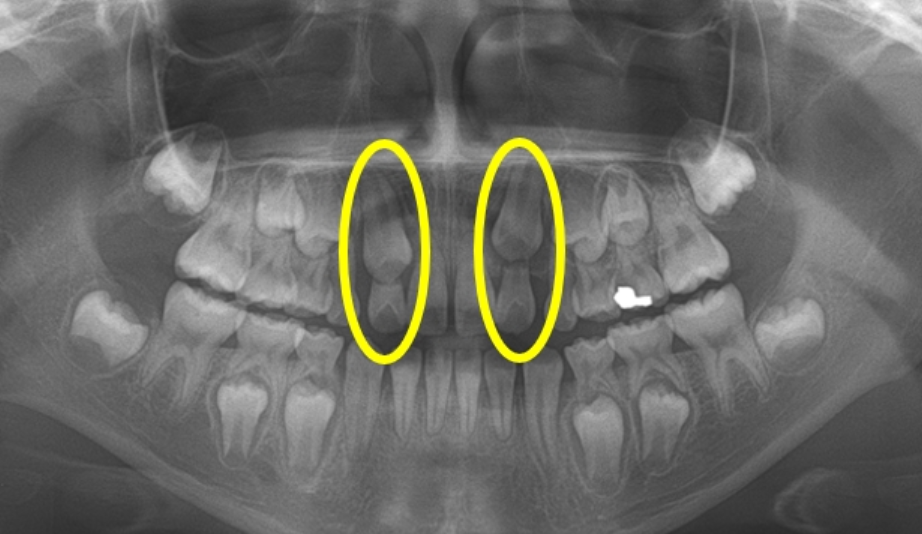

우리 몸은 알면 알수록 신기한 것이 참 많습니다. 그중 치아가 가지고 있는 독특한 특징이 있으니 바로 맹출입니다. 치아의 머리 부분이 입 안으로 나와 기능적으로 사용할 수 있는 위치까지 올라오는 것이 바로 치아의 맹출입니다. 치아는 턱뼈 속에서 머리 부분부터 만들어지기 시작해 뿌리가 만들어지면서 맹출 하게 됩니다. 아이들의 방사선 사진을 보면 뼛 속에 수많은 치아의 씨앗이 보이는 이유가 바로 그런 이유입니다. 치아의 맹출은 단순히 치아가 나오는 것을 떠나 턱뼈의 발육, 안면골격의 성장과 발육과 큰 연관이 있기 때문에 맹출의 장애가 있지 않은지 주기적인 검사가 필요합니다.

유치와 영구치 모두 맹출 하는 시기와 순서가 정해져 있습니다. 약간의 차이가 있기는 하지만 대부분 유전적으로 정해진 대로 맹출 하게 됩니다. 하지만 여러 원인들에 의해 이런 시기와 순서에 문제가 생기거나 나오지 못하는 경우가 생길 수 있습니다. 치아가 제대로 나오고 있는지에 대한 정보는 반드시 방사선 사진으로 확인해야 합니다. 미맹출 치아가 다른 치아와 겹쳐서 보이는 경우에는 CT촬영이 필요할 수도 있습니다.

소아치과 환자 10명 중 한 명 꼴로 맹출장애가 있으며 가장 빈번한 위치는 송곳니다.